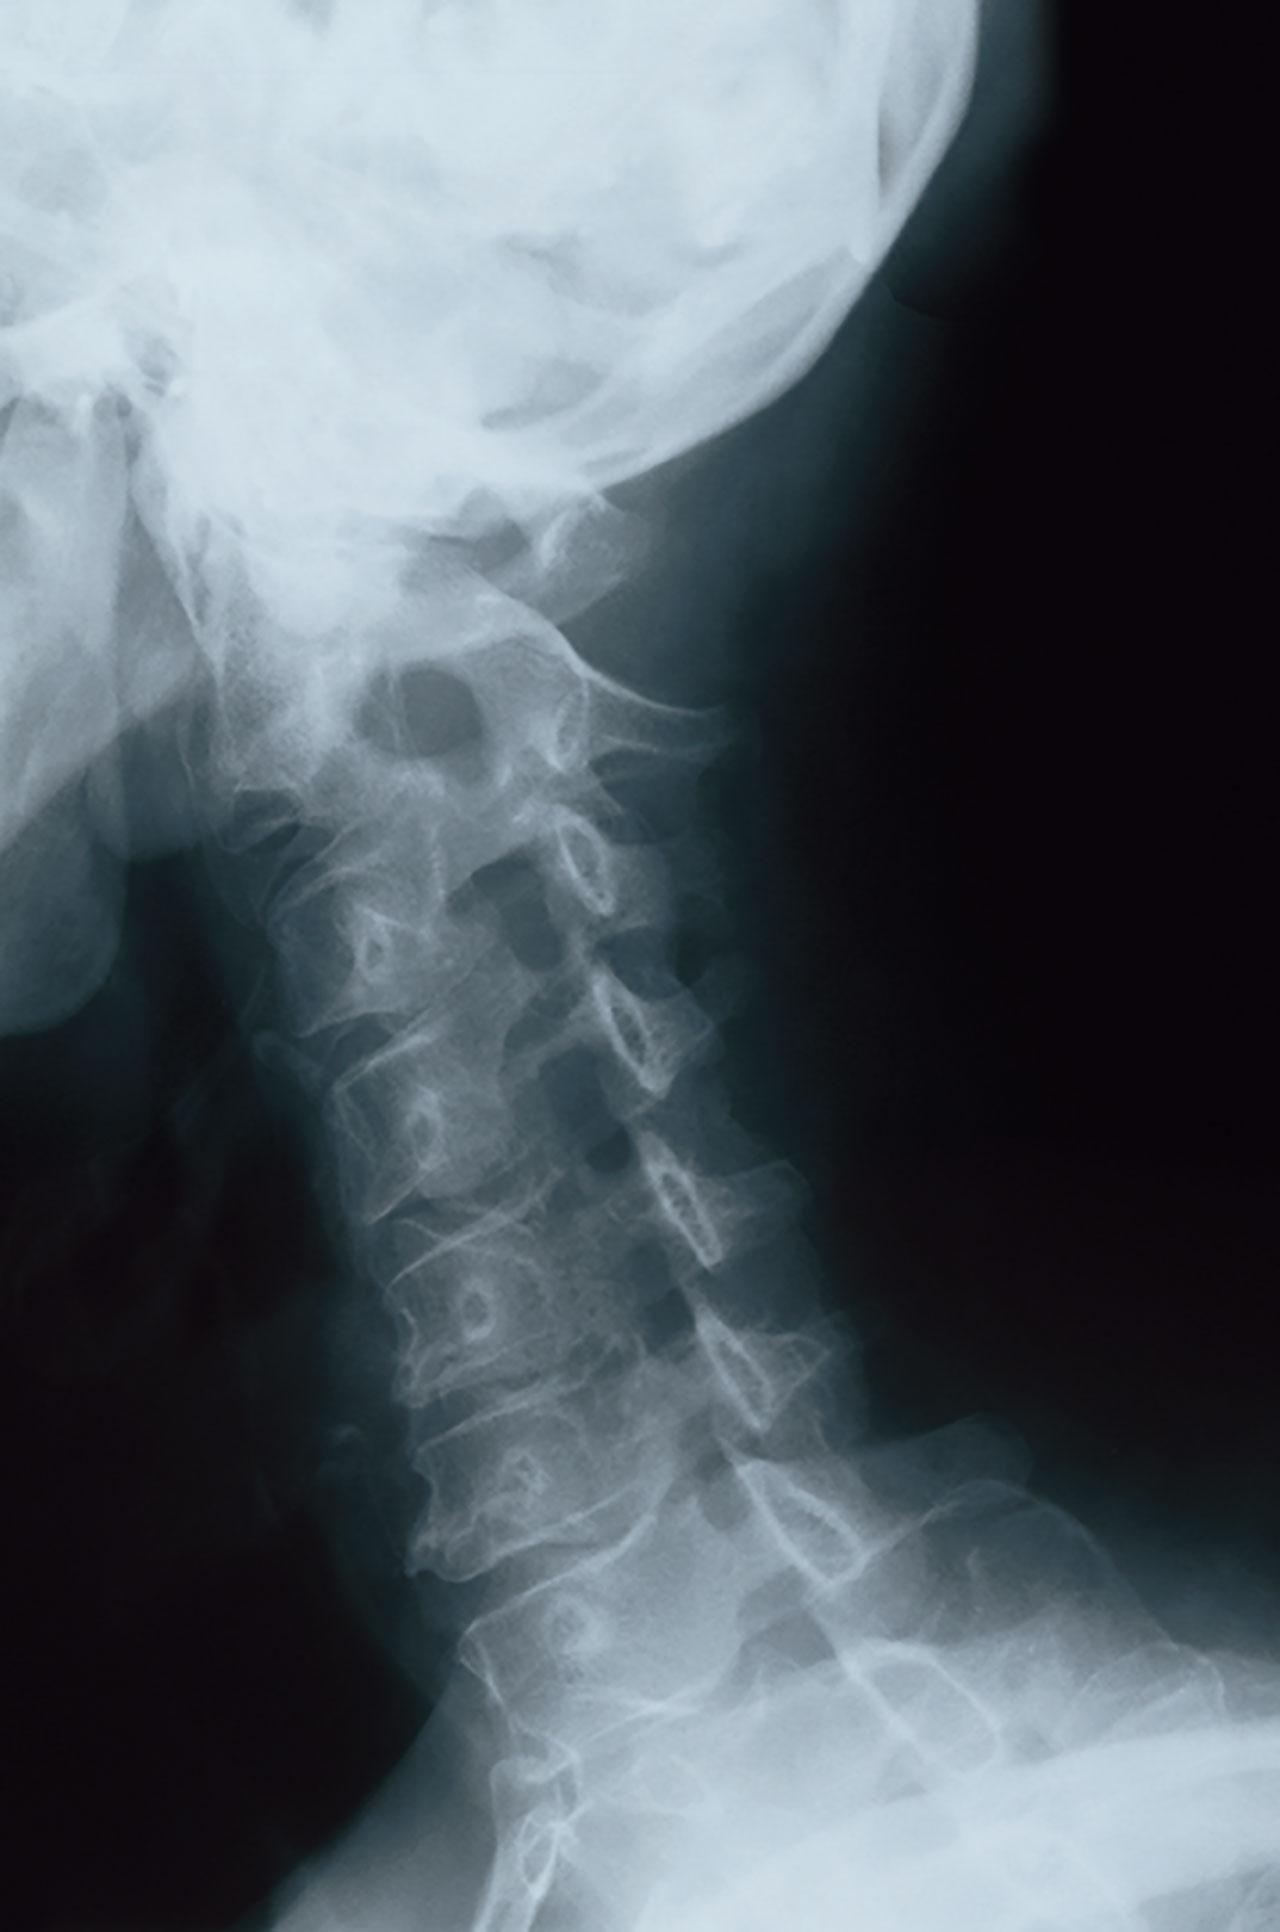

ส่วนมากจะใช้การซักประวัติและตรวจร่างกายก็สามารถวินิจฉัยได้ จะมีการส่งผู้ป่วยไปตรวจเพิ่มเติมก็ต่อเมื่ออาการไม่ดีขึ้น มีข้อบ่งชี้ในการผ่าตัด หรือไม่แน่ใจในการวินิจฉัย โดยทั่วไปมักเริ่มจากการถ่ายภาพทางรังสีก่อน เพื่อประเมินดูตำแหน่งของกระดูกคอ ถ้าต้องการดูโครงสร้างภายใน รวมทั้งหมอนรองกระดูกและเส้นประสาทโดยตรง จะต้องตรวจแบบ MRI ซึ่งจะช่วยในการวินิจฉัย การพยากรณ์โรค และวางแผนการผ่าตัดได้ดี